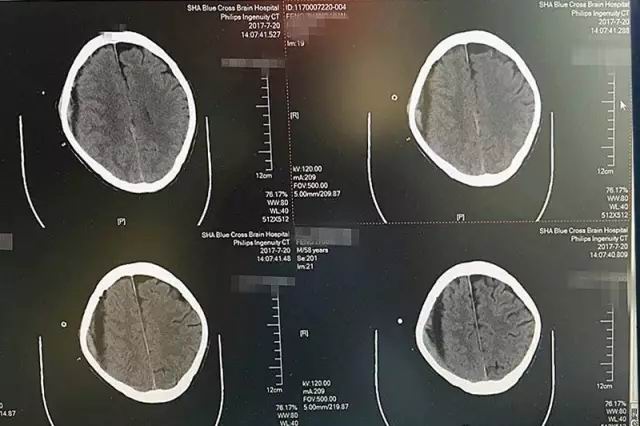

第一天,术中引流出暗红色血液120毫升左右,脑CT影像显示,血肿大部分被吸收。

第二天,又引流出90毫升暗红色血液,术后CT显示血肿基本清除干净。

第三天,血肿顺利被清除,就像工兵搬走了地雷,警报解除。

红圈处为高密度引流管,进入颅内约1.2厘米,后部为放射状伪影

患者术后CT影像显示:血肿基本被吸收